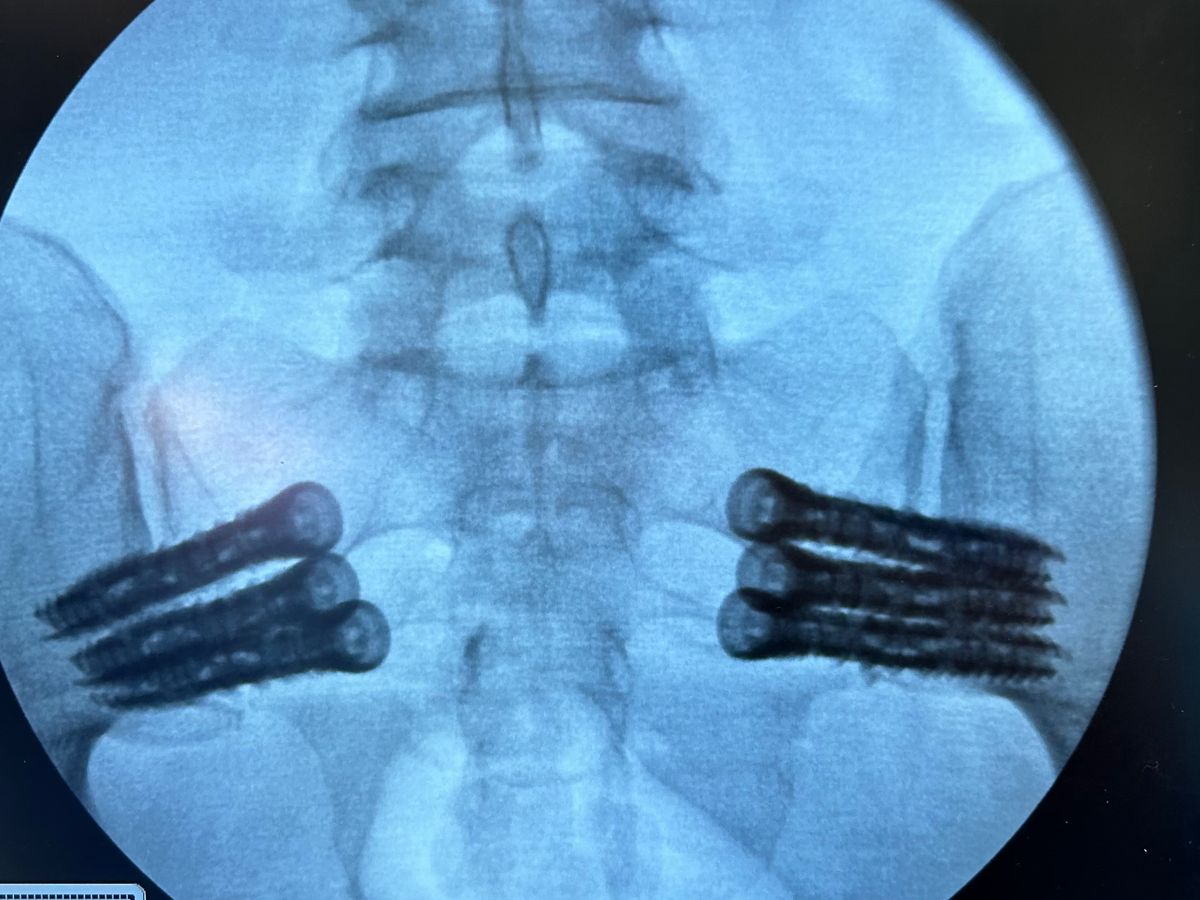

Hi there! My name is Candace! I had surgery on the 23rd of May to repair my SI joints and had 6 screws put in my hips. Unfortunately early morning on June 3rd, I fell and broke my hip right next to my new hardware. Thankfully they didn’t have to redo my surgery or do an additional surgery but I am currently basically bed bound. I can walk a little with my walker but for the most part they don’t want me putting a lot of weight on it in order for it to heal properly. So unfortunately that means I cannot work. I manage a locally owned hardware store and my boss has been wonderful about making sure the store is covered while I’m out, but that also means I have no money coming in. But the bills don’t stop. I know I’ll be out of work for a while so I’m worried about things getting behind. I’m currently trying to find something I can do from home that will make money but it’s not an easy thing to find. I don’t like asking for help ever (you can ask any of my friends or family), but I’m having to put my pride to the side on this. Thank you for taking to the time to read my story and I pray whatever you bless me with, comes back to you ten fold!! ❤️